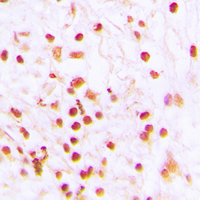

- Experimental details

- Immunohistochemical analysis of ERCC6 staining in human lung cancer formalin fixed paraffin embedded tissue section. The section was pre-treated using heat mediated antigen retrieval with sodium citrate buffer (pH 6.0). The section was then incubated with the antibody at room temperature and detected using an HRP conjugated compact polymer system. DAB was used as the chromogen. The section was then counterstained with hematoxylin and mounted with DPX.